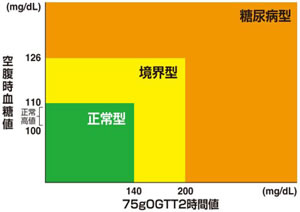

糖尿病:

糖尿病患者は、統計的に歯周疾患を既往している率が高く、糖尿病併発症として歯周疾患は6番目に位置付けられています。

【血糖値】

①空腹時血糖値≧126mg/dL

②75g経口糖負荷試験(OGTT)2時間値≧200mg/dL

③随時血糖値≧200mg/dL

【HbA1c】

④HbA1c(NGSP)≧6.5%

糖尿病が歯周病を含めた感染症を悪化させることはよく知られていますが、歯周病も糖尿病を悪化させます。歯周病の治療・管理により1型・2型を含めた糖尿病患者では、歯周病の治療を行うことでHbA1cが平均0.4%改善するという報告もあります。

副院長は日本糖尿病協会 歯科医師登録医ですので、なんでも相談してください。